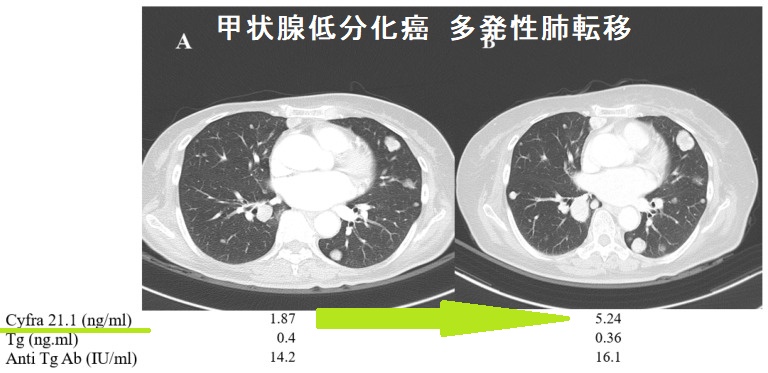

日本がん対策図鑑 | 【EGFR陽性肺がん:一次治療(PFS)】「ラズ。ZX-IPSLAP(1)|テルワールド(NTT中古ビジネスフォン販売店)。A homozygous NOTCH3 mutation p.R544C and a heterozygous。甲状腺癌腫瘍マーカー(サイログロブリン,p53抗体,SCC,CA125,CA19。。